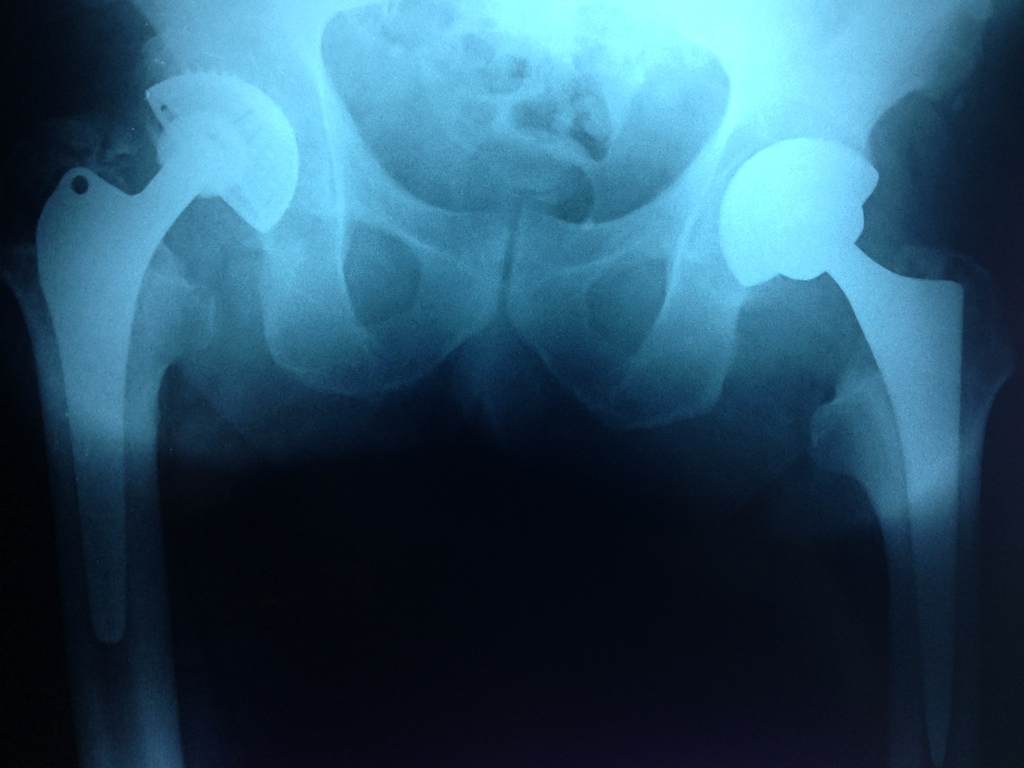

- Il piacere di un paziente che torna … per farsi operare l’altra anca dopo aver avuto soddisfazione con la prima: